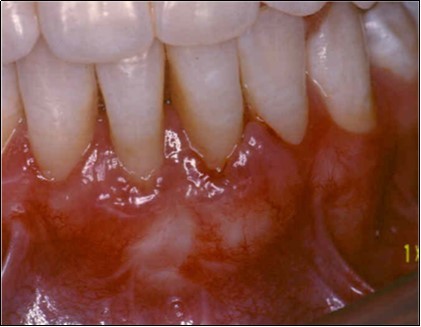

Recipient Site

A partial thickness flap is created with two vertical incisions placed at least one-half to one tooth wider mesiodistally than the area of gingival recession. The coronal margin of the flap is started with a horizontal sulcular incision to preserve all existing radicular gingiva. The interproximal papillae are left intact. The flap dissection is partial thickness leaving connective tissue over the existing bone and / or root surfaces. The root of the involved tooth is carefully scaled and planed until its surface is smooth and hard. Er-YAG laser is then applied to its surface to promote root biomodification, at powers ranging from 25 to 50 mJ/pulse/sec. (Figure 3, Figure 3A).